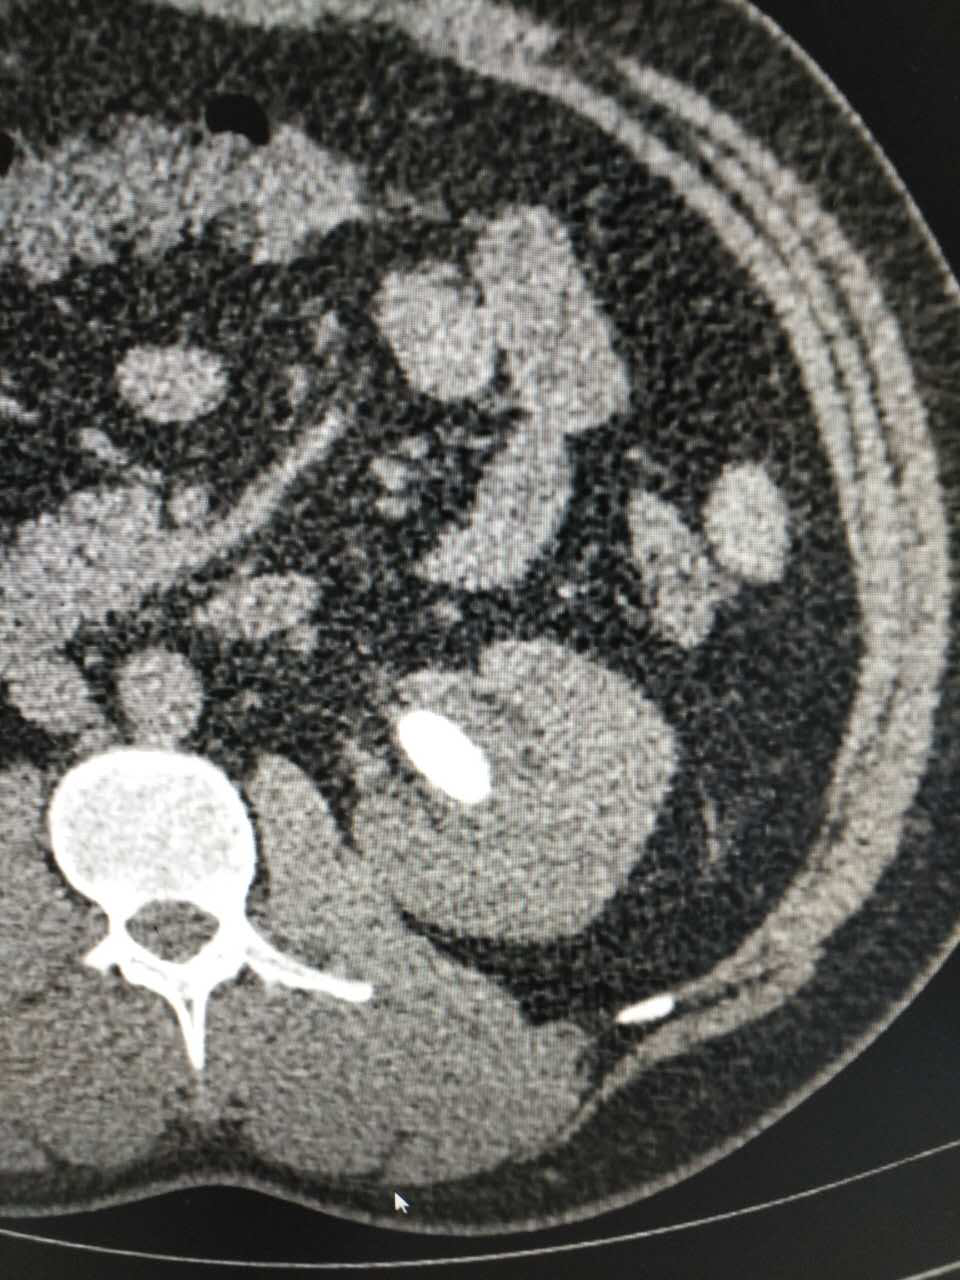

近日,我院泌尿外科成功开展孙氏末端输尿管软镜碎石术,顺利为一例复杂性肾结石患者碎石,手术过程顺利,目前患者已康复出院。

患者,青年男性,因肾结石先后就诊于多家医院,无明显效果后,经多方打听来我院泌尿外科李朝明主任处就诊。李主任在详细了解了患者病情后,最终决定行孙氏末端输尿管软镜碎石术,手术过程顺利,术后患者恢复良好,碎石后排石量达肾结石95%以上,碎石效果明显。

“软镜取石”是继药物排石、体外冲击波碎石、钬激光碎石、经皮肾镜碎石、EMS碎石清石系统之后所开展的又一项新技术。该手术的顺利开展为泌尿系统疾病的诊治提供了新的手段,进一步提升了本科室的微创技术水平,标志着我院泌尿外科在内镜治疗结石方面实现了新的突破,这一技术必将得到更为广泛的应用,为更多患者带来福音。

我院于2015年购置孙氏末端输尿管软镜,泌尿外科李朝明主任先后赴广州医学院附属第一医院、第二军医大学长海医院泌尿外科腔镜中心进修学习,于2015年8月开展输尿管软镜手术,目前已完成近50例,碎石成功率100%,无一例中转开放手术。